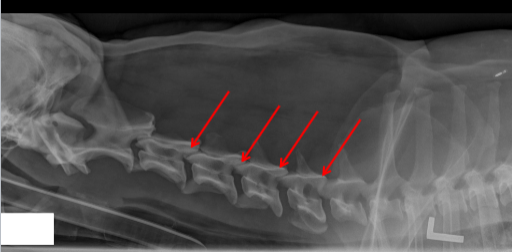

ID

Caudal Articular Process

Cranial Articular Process

Transverse Foramina

Alar Notch

Lateral Vertebral Foramen

Cranial Costal Fovea

Accessory Process